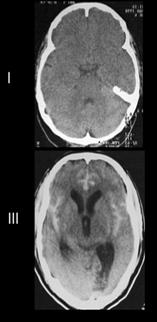

Diagnóstico

Al igual que el ECV isquémico, la prueba inicial siempre debe ser la neuroimagen sin contraste. La tomografía sin contraste es el gold estándar diagnóstico y es mucho más sensible y específica que la resonancia para detectar sangrado.

Tabla 2. Clasificación de Hunt y Hess Tabla 3. Escala de Fisher Figura 6. TAC: Hemorragia subaracnoidea (HSA) (Escala de Fisher)